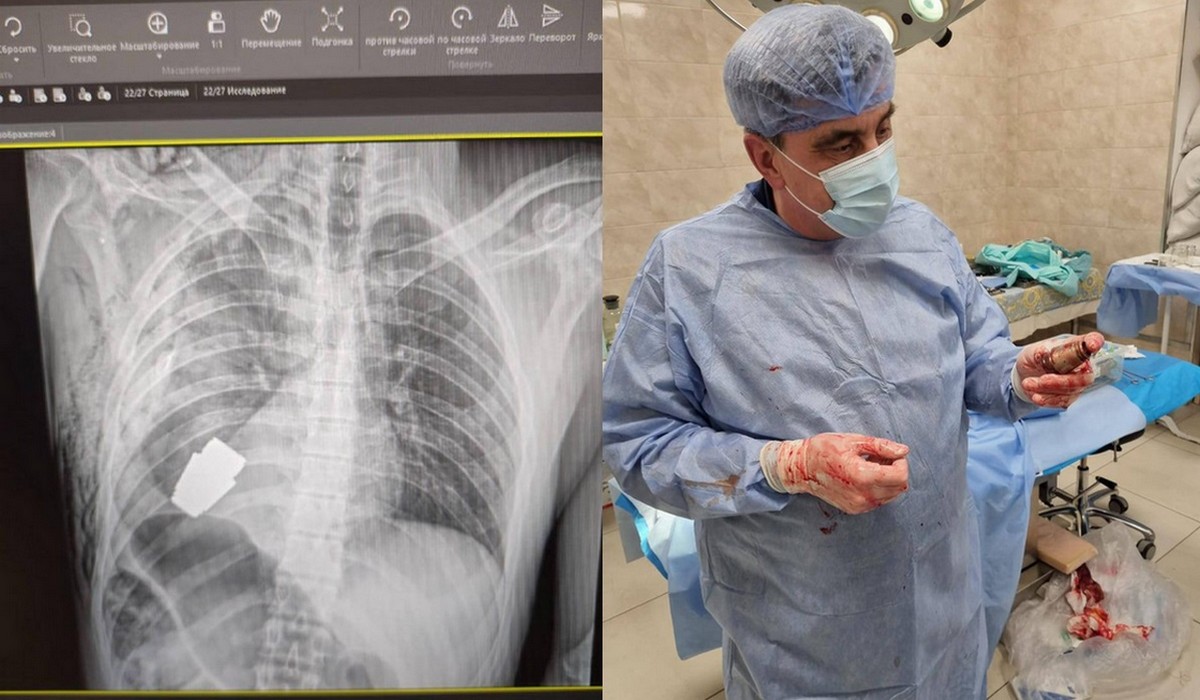

Ukraina: lekarze przeprowadzili operację i wyciągnęli niewybuch z ciała żywego żołnierza

Operacja przebiegła pomyślnie, ranny żołnierz przechodzi teraz rehabilitację